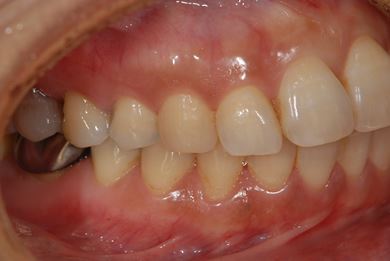

インプラントの症例写真 IMPLANT

骨再生インプラント治療+セラミック治療+歯肉歯槽骨整形

| 性別/年齢 | 女性 / 42歳 | ||||||||||||||||||||||||||||||||

| 主訴 | インプラント治療を受けたい。 | ||||||||||||||||||||||||||||||||

| 治療方針 | 左上奥欠損部分をインプラント治療にて機能的・審美的回復を行う。 | ||||||||||||||||||||||||||||||||

| 治療内容 | インプラント2本(ソケットリフト)、メタルボンドセラミック3本(メタルボンド用土台1本)、歯肉歯槽骨整形 | ||||||||||||||||||||||||||||||||

| 総治療費 | 1,227,713円 | ||||||||||||||||||||||||||||||||

| 治療期間 | 11ヶ月 |